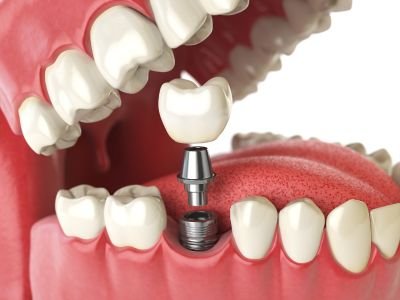

Así inicia esta maravillosa experiencia de viajar por tu sonrisa soñada. Nos reunimos de manera virtual💻 para conocernos y aclarar tus dudas, hacemos un plan de tratamiento según tu necesidades, y expectativas.

Hacemos un tour virtual por nuestra instalaciones para que sientas la seguridad confianza de visitarnos, cuidamos cada detalle.